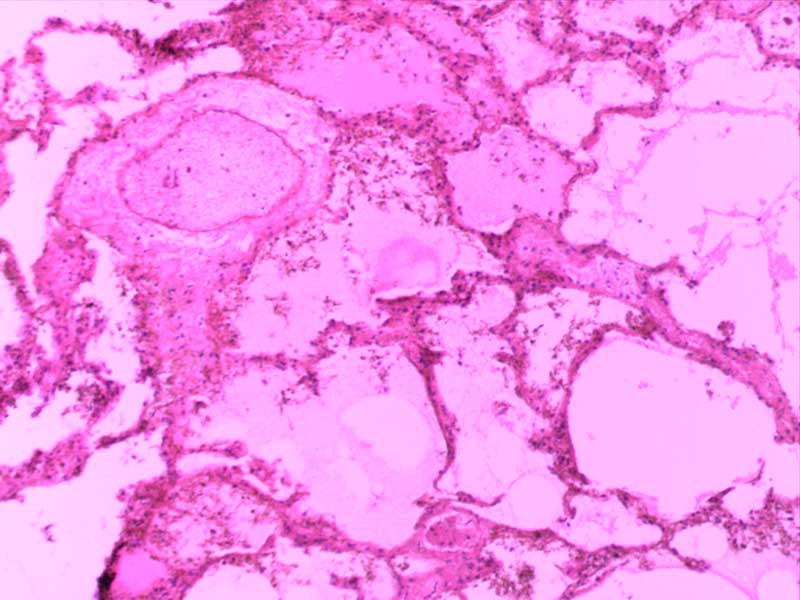

粟粒性肺结核